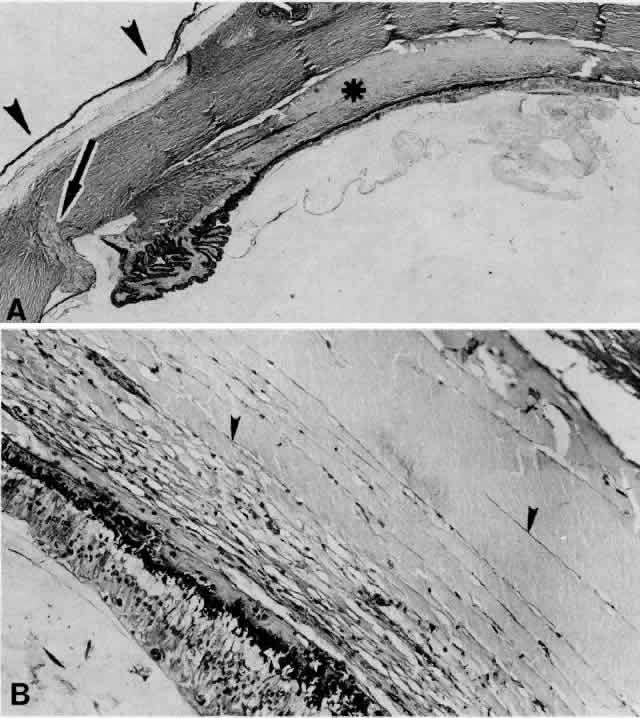

Fig. 8. This choroidal and ciliary body detachment, which occurred after intracapsular cataract extraction, was mistaken for a malignant melanoma.39 A. Iris incarceration in the wound (arrow) and extensive ciliary body effusion consisting of a dense, proteinaceous material (asterisk) (H & E, × 115). B. Effusion of the choroid near the ora serrata by a moderately dense, proteinaceous material without inflammatory cells. Note folds of choroid (arrowheads) (H & E, × 115).

Fig. 10. A. This extensive ciliochoroidal effusion (asterisk), which occurred 4 years after iridencleisis in a 70-year-old man,39 was mistaken for a malignant melanoma. The iris (arrow) is incarcerated in the limbal wound, and a flat, edematous infiltration bleb (arrowheads) is present (H & E, × 25). B. Area of the ora serrata shows a ciliochoroidal effusion with proteinaceous material separating the tangentially oriented collagen fibers (arrowheads) that connect the choroid and ciliary body to the sclera (H & E, × 115).